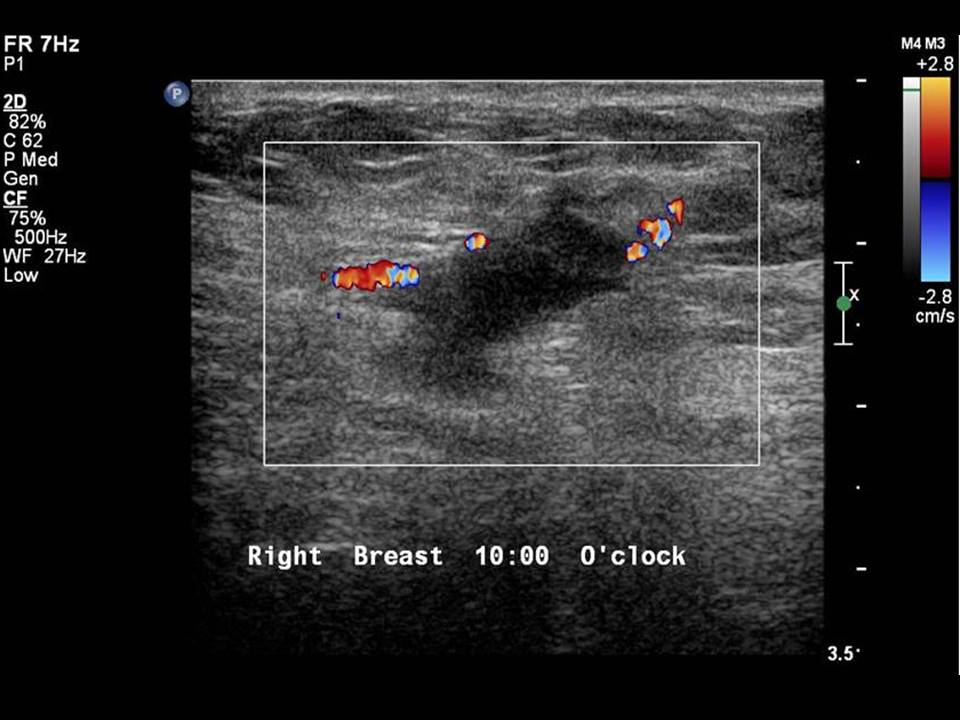

Cureus Utility of Ultrasound Imaging Features in Diagnosis of Breast Spiculated Margins Learn about the breast composition categories, the lexicon for. Spiculated margins are seen in malignant masses. Spiculated masses are defined as masses with lines radiating from their margins (). They describe the extent and possible infiltration of the mass into the surrounding breast parenchyma. The classic description of a breast cancer is a mass with an irregular shape and spiculated. Spiculated Margins.

From screening.iarc.fr